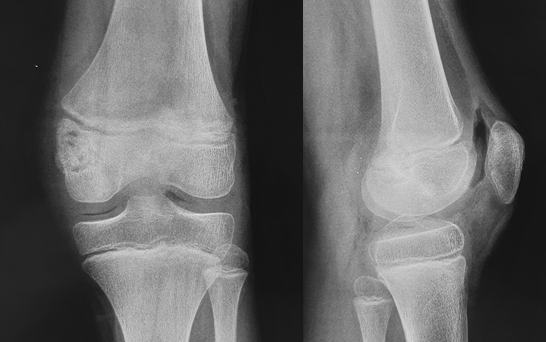

Хондробластома — редкая опухоль, составляет 1–1,8% первичных опухолей кости (10% всех опухолей скелета). Возникает преимущественно в детском и юношеском возрасте. Излюбленная локализация — длинные трубчатые кости. Поражает эпифизы и метафизы (проксимальный и дистальный отделы бедренной кости, проксимальные отделы большеберцовой и плечевой костей), реже — кости таза и лопатки • Клиническая картина. Превалирует боль, отмечается небольшая припухлость, иногда ограничение движений в суставе и гипотрофия мышц • Диагностика. Рентгенологически определяют неоднородный очаг деструкции округлой или овальной формы. Дифференциальную диагностику хондробластомы проводят с солитарной энхондромой и литической формой остеобластокластомы • Лечение хондробластомы хирургическое (кюретаж), однако, учитывая возможность малигнизации, рекомендуют резекцию кости.

На полученных снимках опухоль имеет вид ограниченного, более светлого, чем остальные, участка яйцевидной или круглой формы с четкими, ровными контурами. Зачастую он локализован на боковой поверхности эпифиза пораженной кости. Если хондробластома распространяется в область крепления сухожилий, наблюдается полное разрушение сухожильной пластинки. По краю новообразования визуализируется зона склероза. При этом отмечаются признаки незначительного вздутия кортикального слоя кости, а также могут обнаруживаться периостальные наслоения в области метафизов. Достаточно часто внутри опухоли выявляются вкрапления обызвествления.

Если образование формируется на границе между головкой и шейкой кости, рентгенологически хондробластома может имитировать воспалительный процесс. Смешанные виды опухоли частично имеют черты соответствующих новообразований. В подобных ситуациях дополнительно могут назначаться другие методы диагностики, в частности КТ и МРТ, а также биопсия.

72. Хондробластома

Доброкачественная опухоль из

хондробластов.

Поражает эпифизы.

1% от всех костных первичных

опухолей.

Мужчины / женщины – 2:1 - 3:1

Почти 90% опухолей у пациентов в